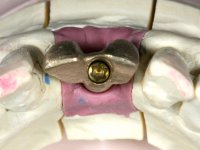

With the implant osteo-integrated with did an impression (open-tray technique) and the dental technician started the construction of a gold framework. The use of an abutment made of a gold alloy allowed us to do a framework with a perfect fit.

During the framework try-in, the color survey was done in order to proceed with the ceramics placement, with a crown and gingiva-components.